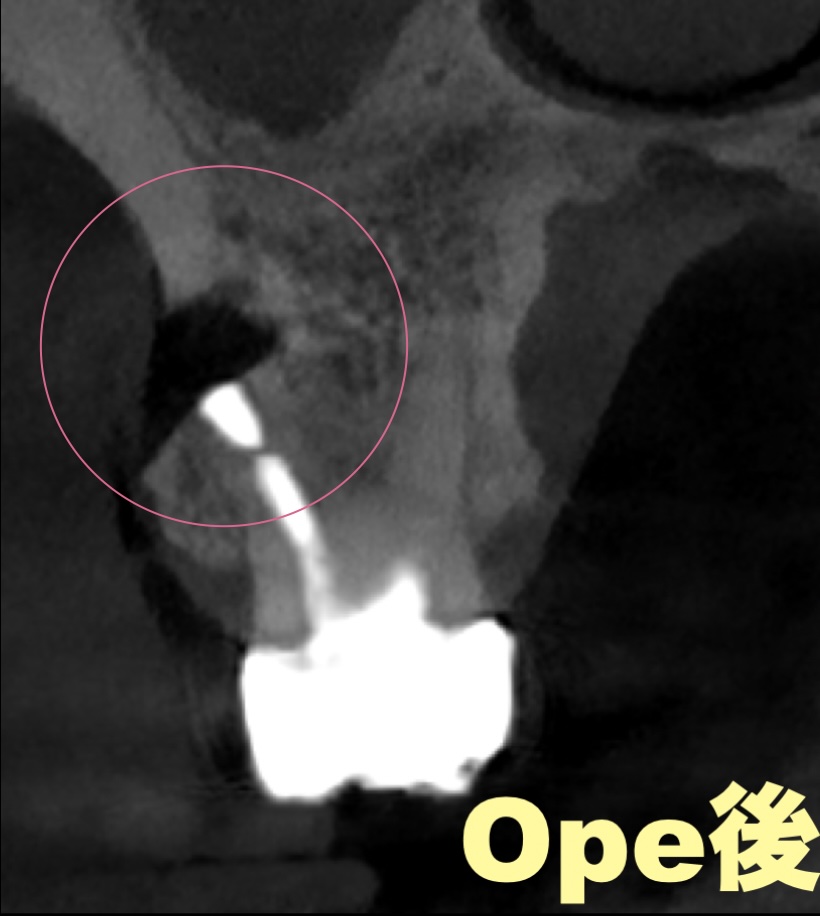

手術前は、歯の根の先に黒い影があり、骨が溶けている部位が確認できました。

9ヶ月後にはその部分が白くなり、骨が再生していることが分かります。

黒い部分は骨が溶けていた部位、

白くなった部分は骨が再生した部位です。